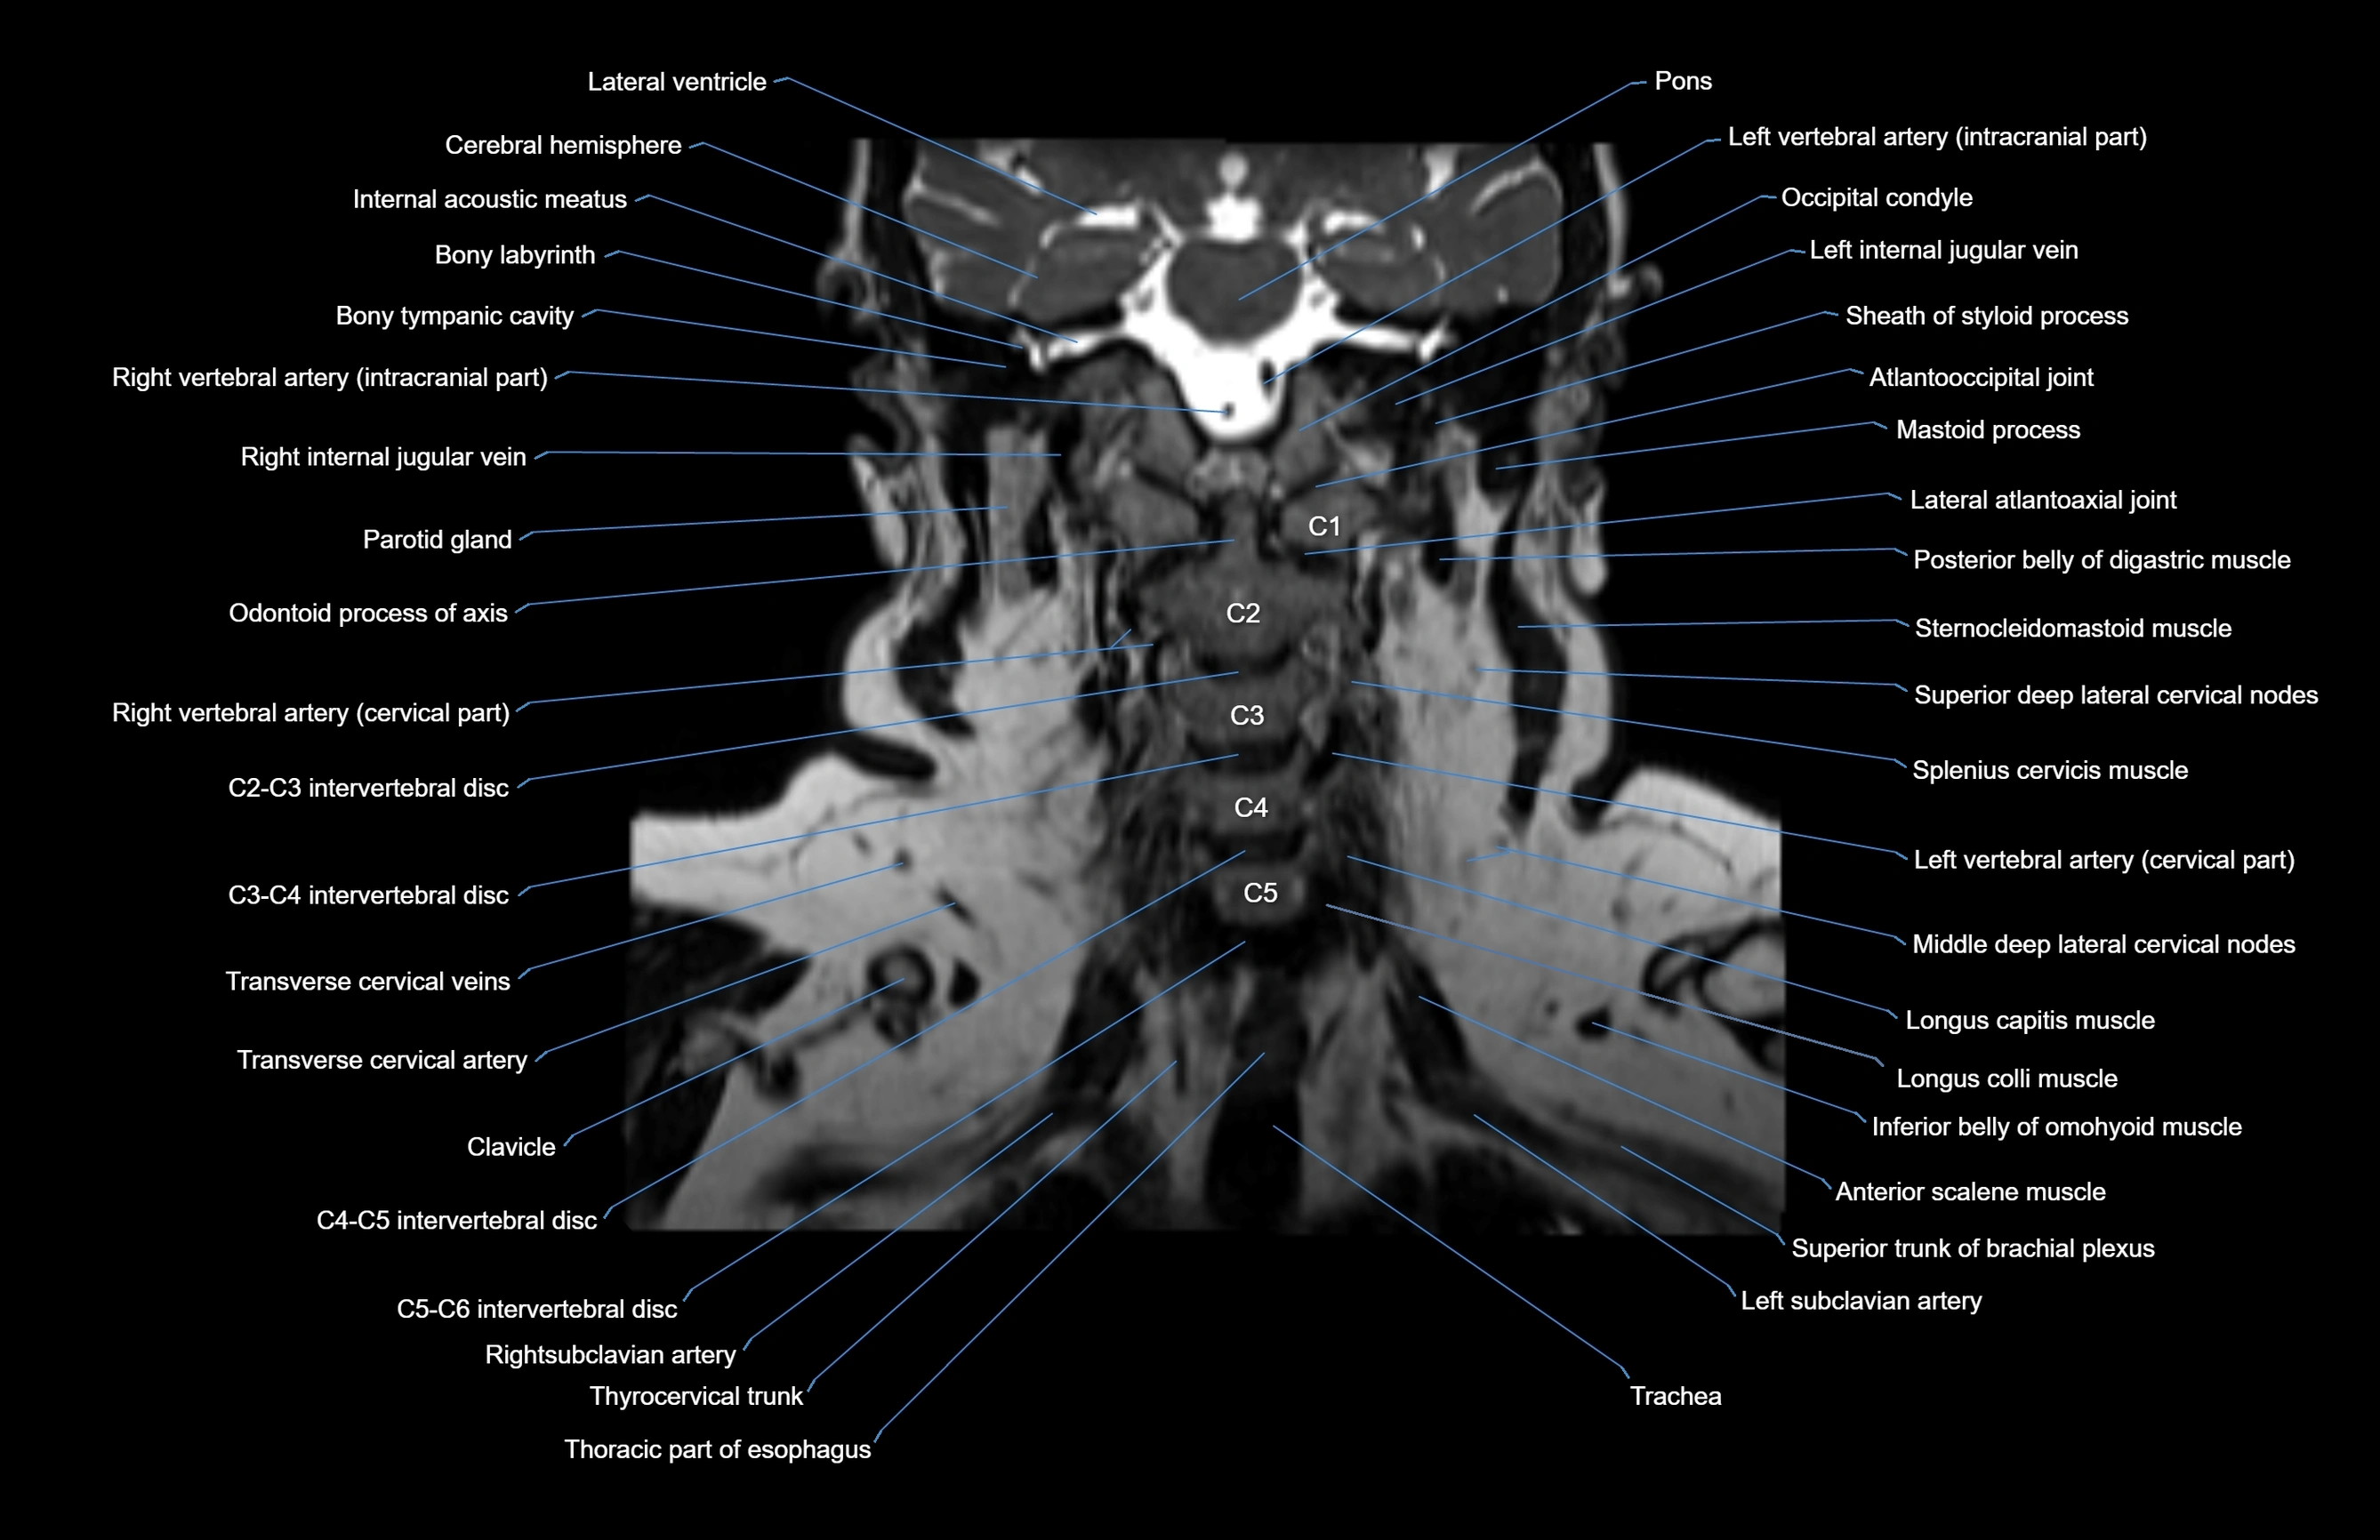

MRI images